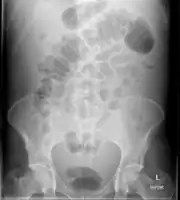

-

Ascites -

Ascites on AXR -